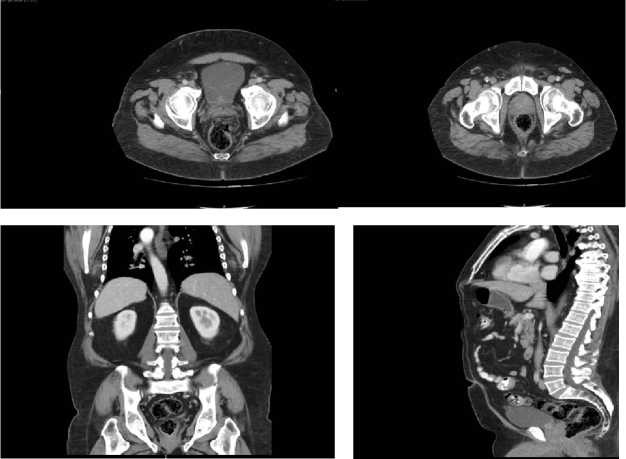

Imágenes de resonancia magnética